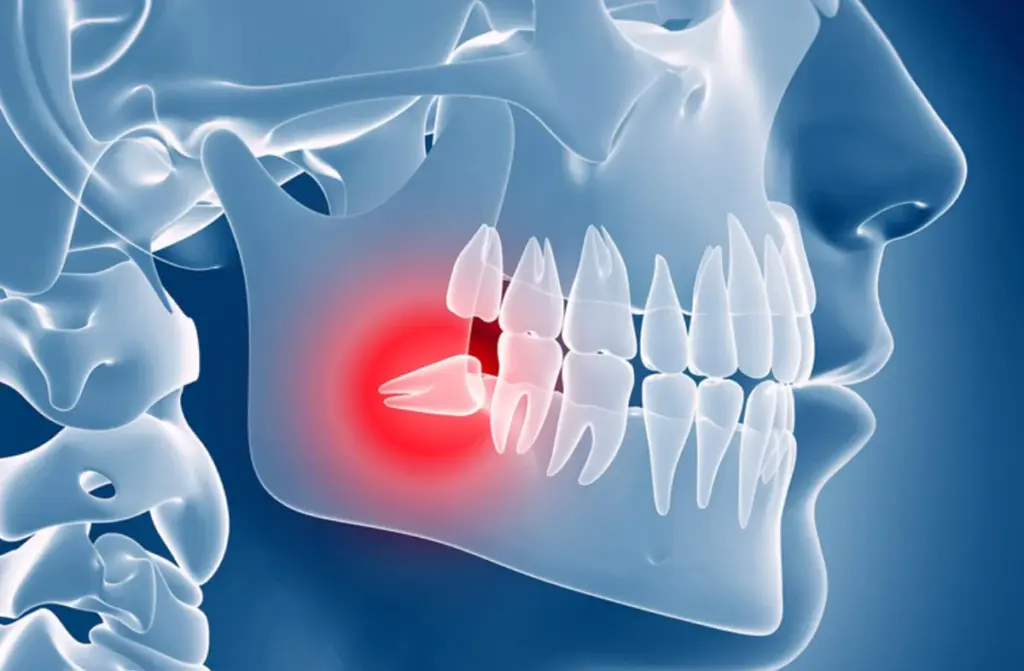

What is impacted wisdom teeth?

Very few people have wisdom teeth which erupt properly and cause no problems. Often, it can grow at an angle because of the lack of space or it can get stuck inside the tissues and that can cause a lot of issues. When the teeth is stuck inside the jaw bone it is called as impacted wisdom teeth. When only half of the teeth is out of the bone and the other half is below the gums , it is called as partially erupted wisdom teeth.